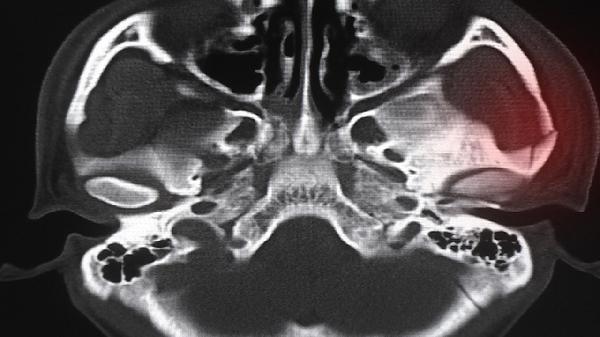

对于腰椎管狭窄或颈椎神经根受压者,该药可通过消除局部软组织水肿,间接减轻神经根压迫导致的肢体麻木、放射性疼痛。常与甲钴胺片等神经营养药物联用增强疗效。